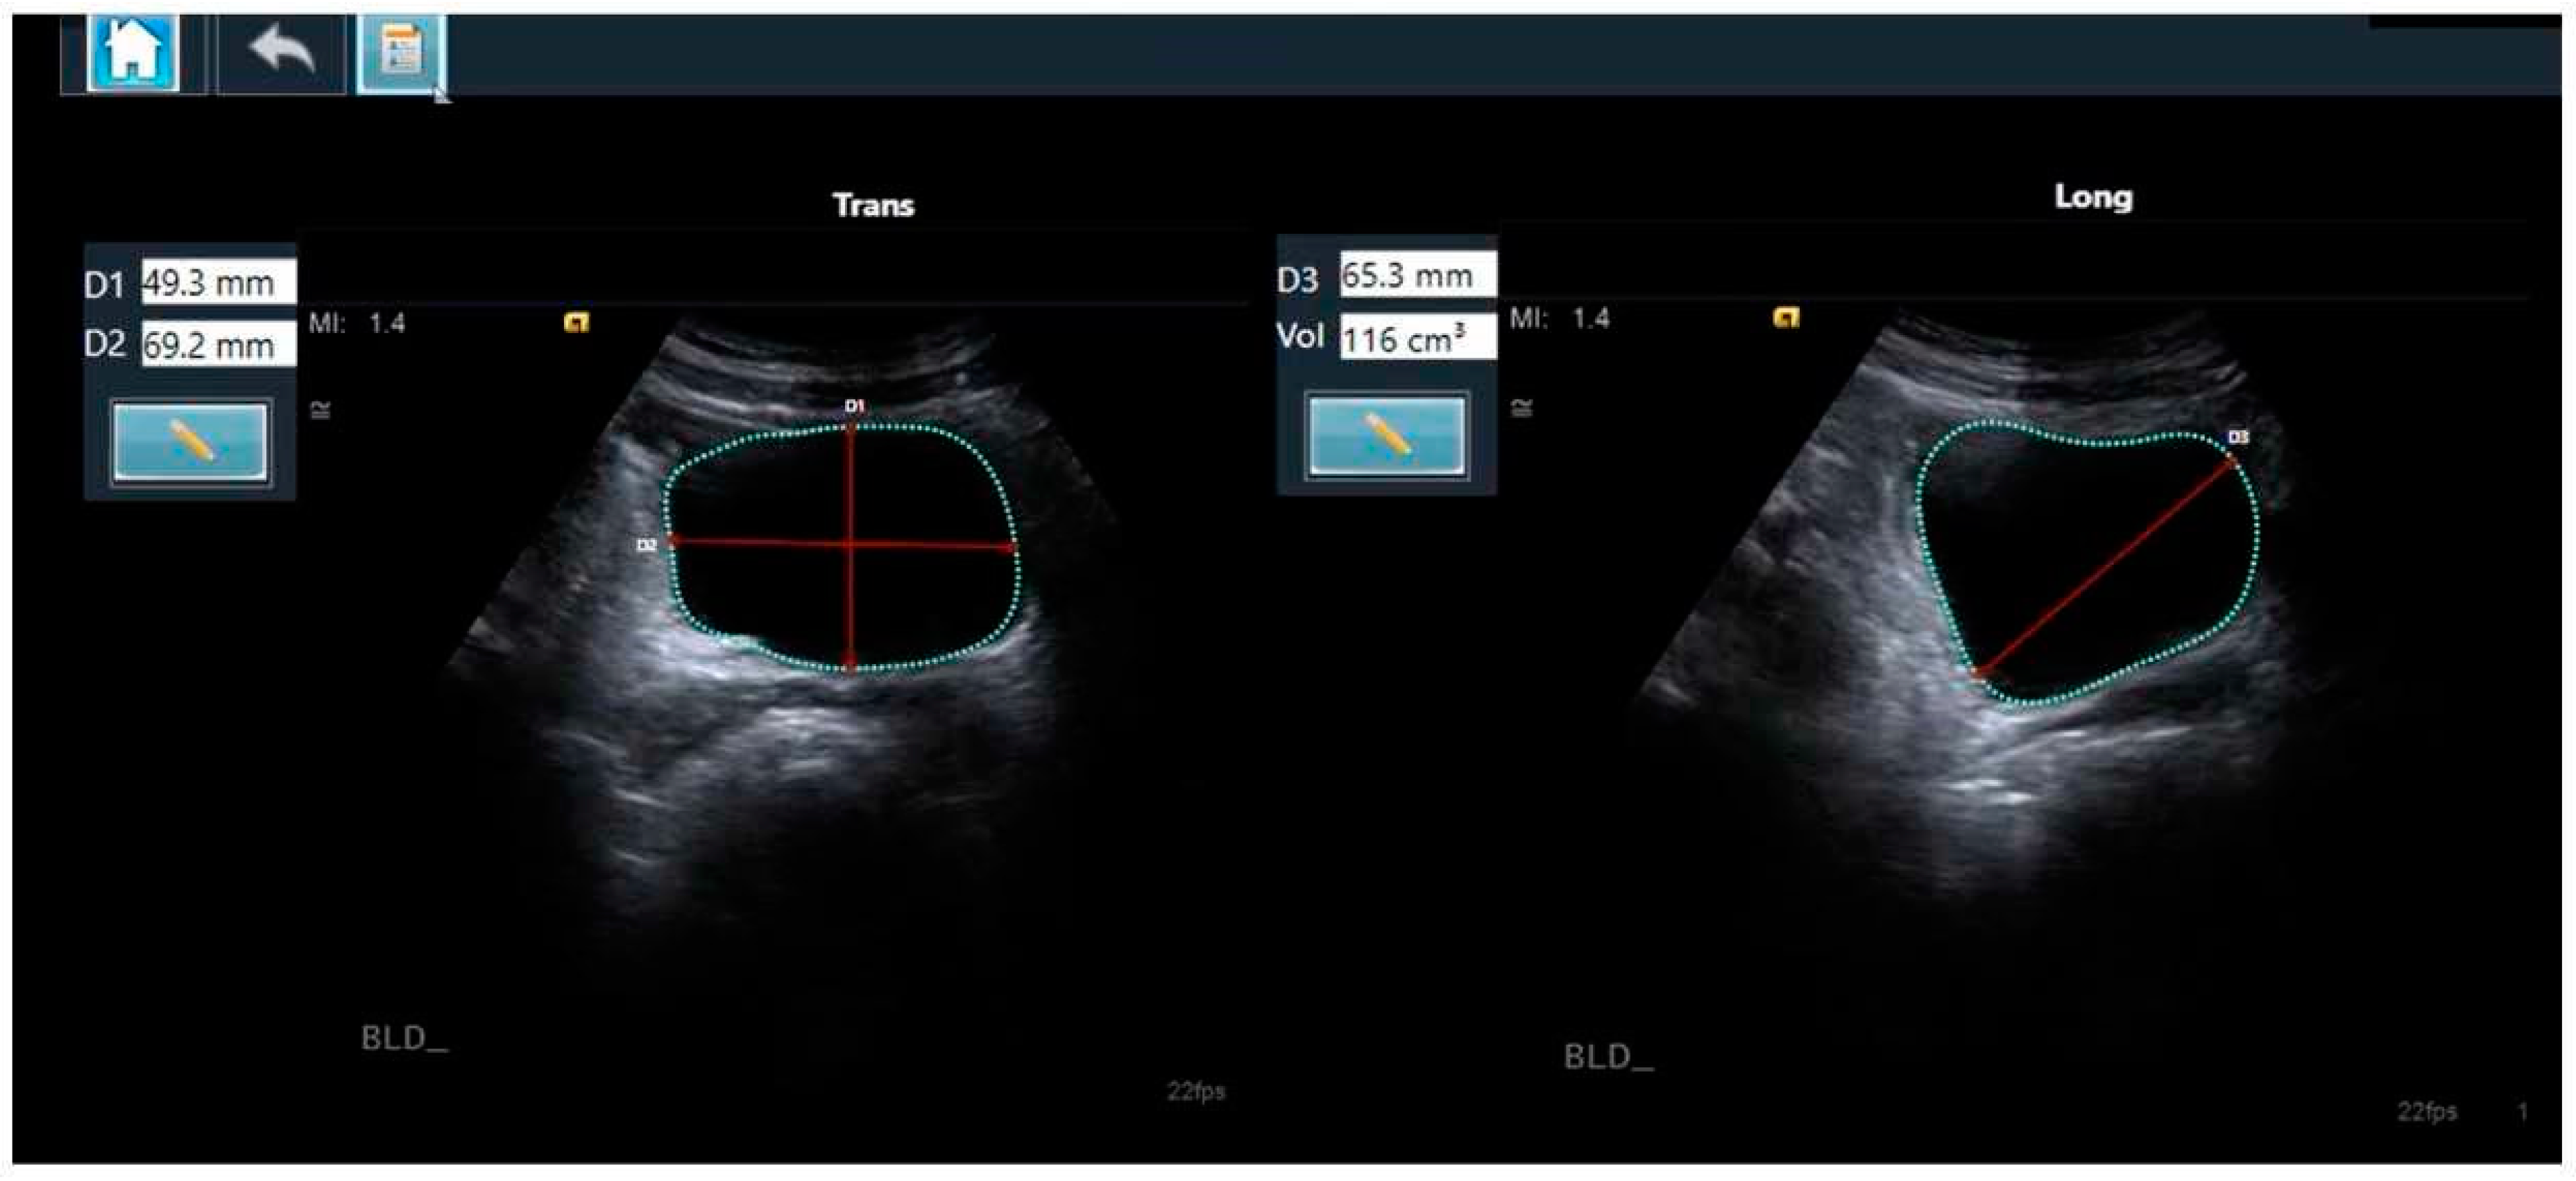

There are several reported methods for the calculation of bladder volume based on 2D ultrasound images, with the prolate ellipsoid formula most commonly used [26,27]. The prolate ellipsoid method uses the three dimensions of the bladder to calculate the volume based on the mathematical formula V = D1 × D2 × D3 × 0.52, (where V is the volume, D1, D2, and D3 are the respective diameters, and 0.52 is the applied correction factor) (Figure 1) [26].

Figure 1.

The automated bladder volume and dimension measurements of transverse (left panel) and longitudinal (right panel) clips, as calculated using the AI-based tool LVivo Bladder, with the prolate ellipsoid method using the three dimensions of the bladder. The red lines represent the individual diameters. The mint-colored shape the automated trace of the outline of the bladder wall.

The AI-based module used was the LVivo Bladder® (DiA Imaging Analysis, Beer Sheva, Israel). This is a commercially available application for fully automated bladder volume measurement, based on 2D ultrasound images. This tool is a decision-support software application that automatically identifies the bladder contours by searching for the dark areas that are regarded as the bladder. The algorithm then determines which area is most likely the bladder, based on edge morphology and heuristics, such as the position, size, and shape of the different areas. The three diameters of the bladder are obtained from the detected contours. The volume is instantly calculated using the prolate ellipsoid method (Figure 1). The manual correction of the bladder border tracings is supported by the application if it is deemed required. In cases of no or minimally recognizable structures that are insufficient for diagnosis, the application will notify that the measurement is not possible.